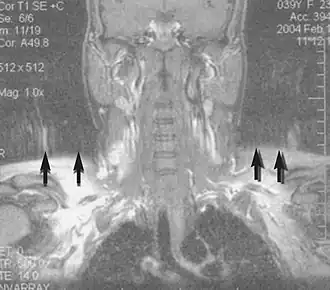

Magnetic resonance angiography (MRA) generates pictures of the arteries to evaluate them for stenosis (abnormal narrowing) or aneurysms (vessel wall dilatations, at risk of rupture). MRA is often used to evaluate the arteries of the neck and brain, the thoracic and abdominal aorta, the renal arteries, and the legs (called a "run-off"). A variety of techniques can be used to generate the pictures, such as administration of a paramagnetic contrast agent (gadolinium) or using a technique known as "flow-related enhancement" (e.g., 2D and 3D time-of-flight sequences), where most of the signal on an image is due to blood that recently moved into that plane (see also FLASH MRI).[53]

Techniques involving phase accumulation (known as phase contrast angiography) can also be used to generate flow velocity maps easily and accurately. Magnetic resonance venography (MRV) is a similar procedure that is used to image veins. In this method, the tissue is now excited inferiorly, while the signal is gathered in the plane immediately superior to the excitation plane—thus imaging the venous blood that recently moved from the excited plane.[54]